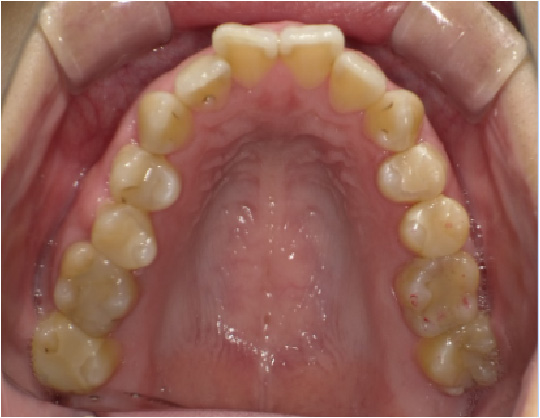

狭い歯列(狭窄歯列)によって、舌が歯列の中に収まらない状態です。

●高口蓋 ●低位舌 ●口呼吸

狭窄歯列(高口蓋)

右のように、狭窄歯列だと舌は、狭い歯列に阻まれて、前方や上方の口蓋に自由に動くことができません。その結果、舌は低い位置(低位舌)にあり、前方に出ず後方に位置するので、気道が狭くなってしまっています。

狭い歯列(狭窄歯列(きょうさくしれつ))

高口蓋(上顎が深い→鼻腔が狭い)

舌が歯列に納まらない→低位舌

歯並びが悪い